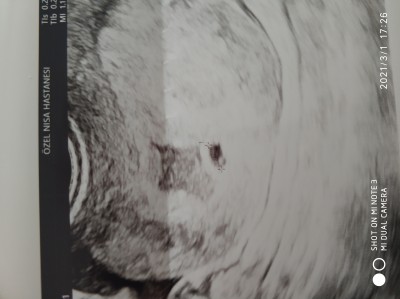

Kızlar bugün geldim doktora beta hcg yavaş artışı olduğu için ayrıntılı ultrasonla bakıldı kese göründü içinde ufak bebekte göründü ama doktor sağlıksız gebelik dedi dış gebelik değilmiş içim rahatladı. Sağlıksız gebelik denip sonradan sağlıklı olabilir mi böyle yaşayanlar bana yardımcı olabilir mi acaba bu üçüncü düşük yapışım olcak :(Kızlar fotoğraf yükledim alttan baktığında nokta kadar bebek var gibi görüyorum dedi

Gebelik haftası 5+3

Canım benimde vajinal ultrasonla baktı fotoğraf yükledim şimdi nokta kadar bebek görüyorum dedi. Sağlıksız kese dedi. Beta artışımı yazıyorum hemen hemen 18 şubat 200, 22 şubat 400, 26 şubat 775 28 şubat 1209 :(